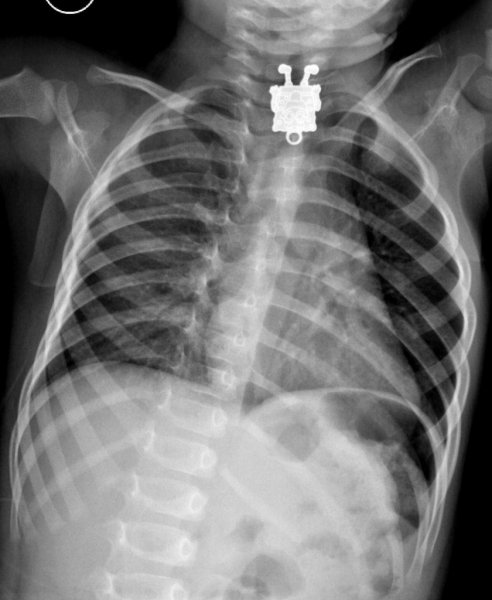

Специалисты по рентгеновской диагностике регулярно сталкиваются с посторонними предметами внутри тела человека. Обычно лишние предметы попадают в пищеварительную систему из-за неосторожности при еде или во время неудачных любовных игр. Почти всё удается вытащить — с хирургическим вмешательством или без него. выбрал самые необычные находки радиологов, которыми они делились на сайте Radiopaedia.org.